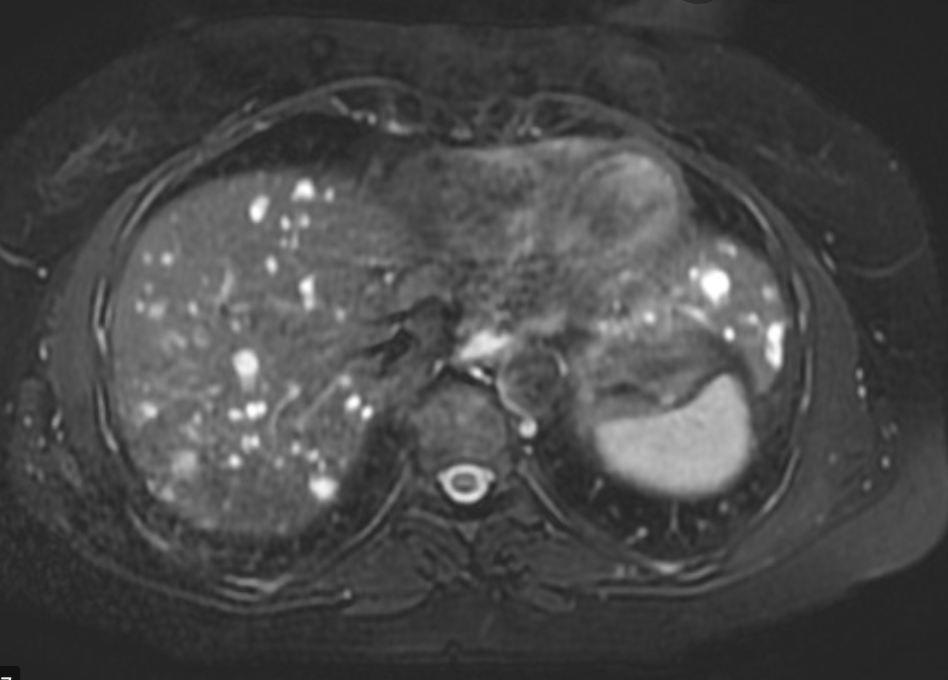

what is this?

Biliary cystadenoma

- uncommon, multilocular cystic liver mass that originates in the bile duct and usually occurs in the right hepatic lobe.

- Typically occurs in women

- h/o chronic abdominal pain

- it may represent a congenital anomaly of the biliary anlage

- COMPLICATIONS

- Malignant transformation cystadenocarcinoma occurs

- IMAGING FEATURES

- well defined and cystic

- internal sepations

- The cyst walls and any other soft tissue components typically enhance with contrast

- variable appearance on MRI depending on the protein content of the fluid and the presence of an intracystic soft tissue component.